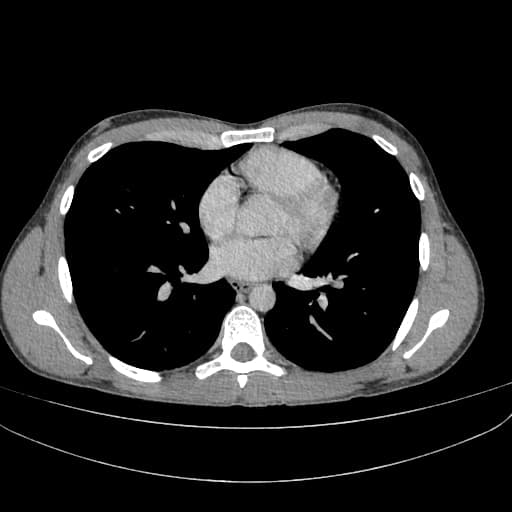

Cộng hưởng từ ruột (MRI enterography) phải dừng sớm khi phát hiện hình cản quang kim loại tại vùng chậu giữa và hố chậu trái.

Do hình cản quang kim loại, yêu cầu thực hiện MRI ruột được chuyển sang chụp cắt lớp vi tính (CT).

Chụp X-quang bụng không chuẩn bị (CT scanogram) cho thấy hình tăng tỷ trọng (metallic density) tại nửa bụng phải, cụ thể là ống nội soi dạng viên nang bị kẹt (trapped capsule endoscope). Hình ảnh này được xác nhận nằm trong lòng ruột (intraluminal), trong một quai hồi tràng.

Hình cản quang kim loại ban đầu xuất hiện ở vùng chậu giữa và hố chậu trái, nhưng thật đáng ngạc nhiên là ống nội soi bị kẹt lại nằm trong lòng ruột, bên phải, và có thể đã di chuyển trong quá trình làm MRI.